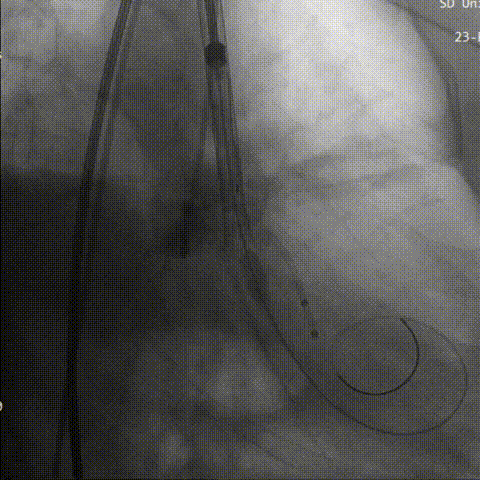

第二次定位

释放到工作

造影评估下瓣环上2mm定位,缓慢释放,瓣膜下滑到瓣环平面水平,瓣膜位置良好,继续释放到工作位进行评估,反流较为显著。决定再次回收。

回收后第三次进行瓣上2mm定位,确定释放位置稳定后没缓慢是放到工作位,猪尾导管造影显示无反流。

第三次定位

工作位评估